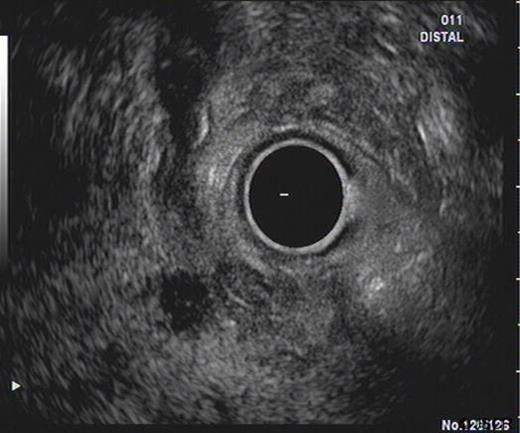

SC was a 46 yr old gentleman who was referred from his district hospital with a six month history of upper abdominal pain and weight loss. His past medical history included a prolapsed lumbar disc and he was not on any regular medications. A family history revealed that his grandfather had gastric cancer. He was a non-smoker and had a moderate alcohol intake. A Computer Tomography (CT) scan of his abdomen and pelvis revealed no significant abnormalities except for changes suspicious of duodenal diverticular disease. Prior to his consultation he had endoscopies of both his upper and lower gastro-intestinal tracts which were reported as revealing no abnormalities. An Endoscopic Retrograde Cholangio-Pancreatogram (ERCP) was precluded due to the difficulty of the duodenal diverticulum obscuring the ampulla of Vater. A subsequent Endoscopic Ultrasound Scan (EUS) revealed an 8mm soft tissue lesion in the distal common bile duct (CBD) causing dilatation of the pancreatic duct (Figure 1). Elastography showed this to be a firm mass. FNA sample were subsequently taken from the mass which revealed no malignant cells. The HPB MDT meeting felt that although the lesion could be benign, a malignant process could not be excluded thus a Whipple’s procedure was advised.

An ultrasound prior to this clinic appointment revealed a dilated Common Bile Duct (CBD) of up to 10mm, a distended thin walled gallbladder, no calculi and a normal pancreatic body. The head of the pancreas was not visualised. Laboratory tests from the GP revealed an elevated bilirubin of 150 umol/L. The CT of his abdomen and pelvis confirmed a dilated CBD and some areas of focal calcification on the head of the pancreas (Figure 3). The EUS demonstrated a thickened distal CBD with a 1.5cm hypoechoic lesion in the pancreatic head (Figure 4). The HPB MDT meeting suspected a malignant lesion and felt that a Whipple’s procedure would offer the best chance of cure.

EUS demonstrating lesion at the pancreatic head with thickening of distal CBD